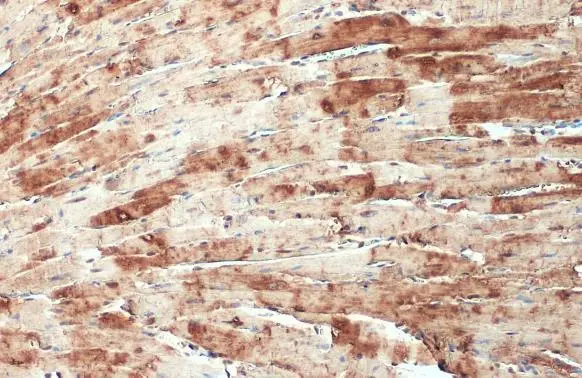

- Delivery Days Customer9

- Application Supplier NoteWB: 1:500-1:3000. ICC/IF: 1:100-1:1000. IHC-P: 1:100-1:1000. *Optimal dilutions/concentrations should be determined by the researcher.Not tested in other applications.

- ApplicationsImmunoFluorescence, Western Blot, ImmunoCytoChemistry, ImmunoHistoChemistry, ImmunoHistoChemistry Paraffin